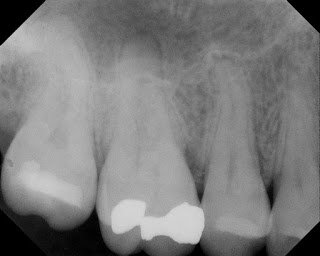

This patient came to our office in early 2010. She was reporting throbbing pain to temperature that had been bothering her for a couple of weeks. She also reporting biting pain. Diagnostics found #3 was normal to cold test, normal to probing, mild pain to percussion, pain to biting pressure. DX; #3 reversible pulpitis with symptomatic apical periodontitis and cracked tooth syndrome. We decided to treat endodontically before a crown would be placed.

Upon accessing the pulp, we found a stained crack on the mesial and smaller crack on the distal. Pt was informed that these cracks would not be completely removed, and would affect the long term prognosis for the tooth. The patient, understanding that the prognosis is guarded, elected to preserve the tooth as long as possible by completing the RCT and placing a crown.